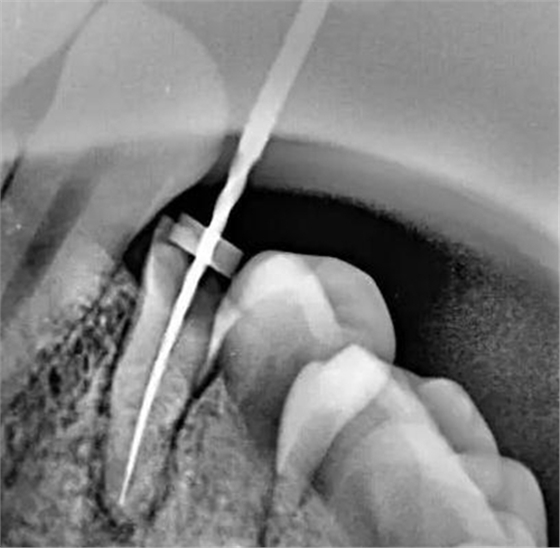

牙根內(nèi)外吸收的原因不同,治療方法和預(yù)后也不一樣。因此,應(yīng)根據(jù)X線和臨床表現(xiàn),區(qū)別內(nèi)外吸收,選擇適應(yīng)的治療方法,用X線根尖片和咬合片的表現(xiàn)區(qū)分牙根內(nèi)外吸收;內(nèi)吸收邊界清楚光滑,形狀多對(duì)稱,吸收部位根管粗大;外吸收邊界粗糙,密度不一,呈蠶食壯,形狀多不對(duì)稱,在破壞未穿通根管前,仍能尋找到根管的原始輪廓。偏移投照時(shí),內(nèi)吸收與根管的位置關(guān)系不變,而外吸收部位發(fā)生變化。

內(nèi)吸收是從髓腔或根管內(nèi)壁開始,與牙髓炎癥和細(xì)菌感染有關(guān)。一般無癥狀,多為X線照相時(shí)發(fā)現(xiàn)。應(yīng)盡早行根管治療,去除感染組織后,預(yù)后良好,否則進(jìn)一步發(fā)展會(huì)造成根管壁的穿孔。徹底去除內(nèi)吸收部位的感染組織較為困難,充分沖洗或超聲蕩洗是有效的清潔方法,并在根管內(nèi)封Ca(OH)2蝴劑1周后再根充。由于內(nèi)吸收過大,根管壁很薄,應(yīng)避免過大壓力,要選用Ca(OH)2基質(zhì)的蝴劑與牙膠根充,根管壁穿孔較小,可用 Ca(OH)2糊劑根充3個(gè)月,誘導(dǎo)硬組織形成后再根充;或用根管水泥(MTA)根管內(nèi)根充并修補(bǔ)。較大的根管壁穿孔可用MTA從根管內(nèi)或手術(shù)修補(bǔ)。內(nèi)吸收近根尖區(qū)可考慮根尖手術(shù),多根牙可考慮截根術(shù)。